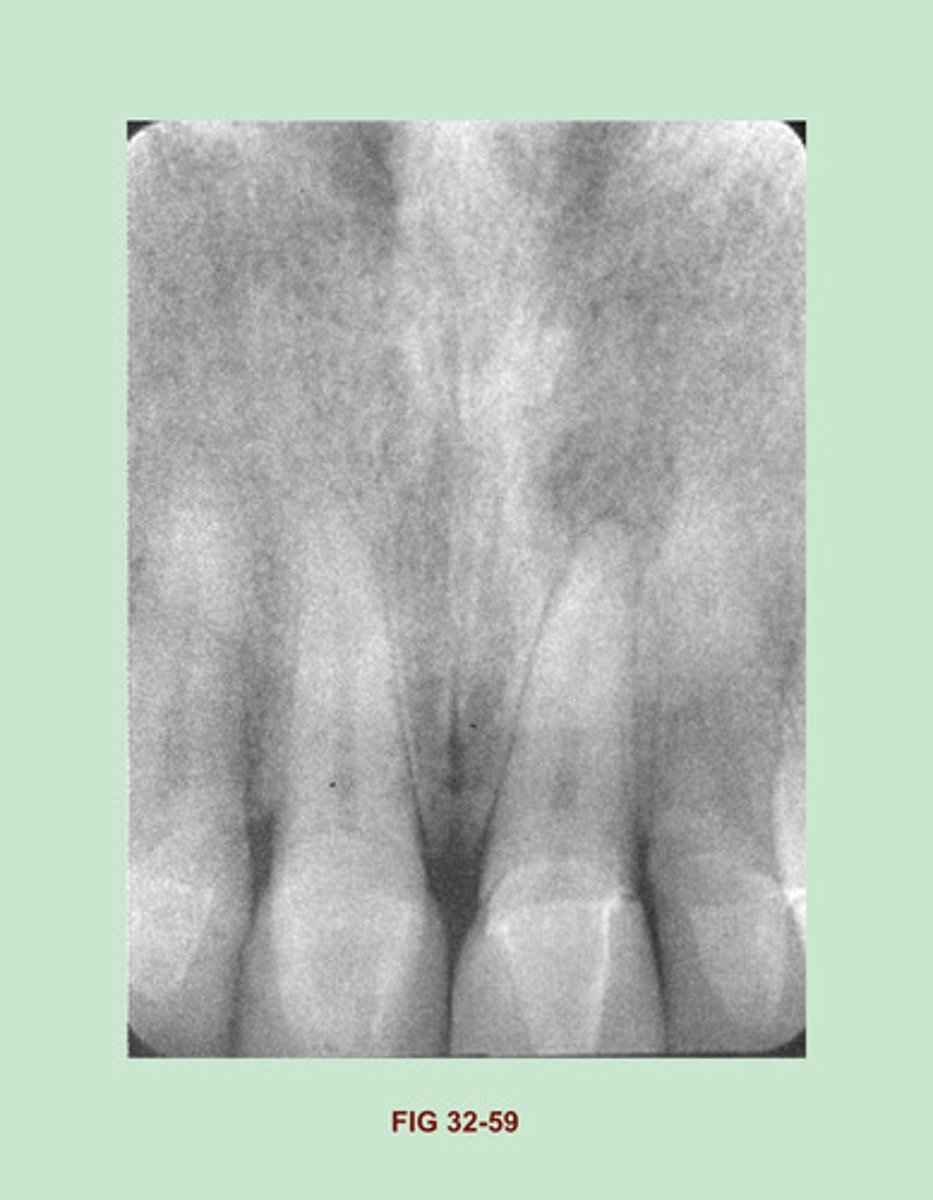

Identify the RESTORATIVE material used in the MAXILLARY ANTERIOR REGION. (Figure 32-59).

Porcelain crowns

Side Notes: Porcelain restorations appear radiopaque on a dental image. unlike metallic restorations, which appear completely radiopaque, porcelain restorations are slightly radiopaque & resemble the radio density of dentin. All-porcelain crowns & bridges appear slightly radiopaque on a dental image. A THIN radiopaque line outlining the prepared tooth may be evident through the slightly radiopaque porcelain crown.

This THIN LINE represents cement or other dental ADHESIVE material used to adhere the crown to the tooth. the RADIODENSITY of an all-porcelain bridge appears identical to that of the all-porcelain crown.